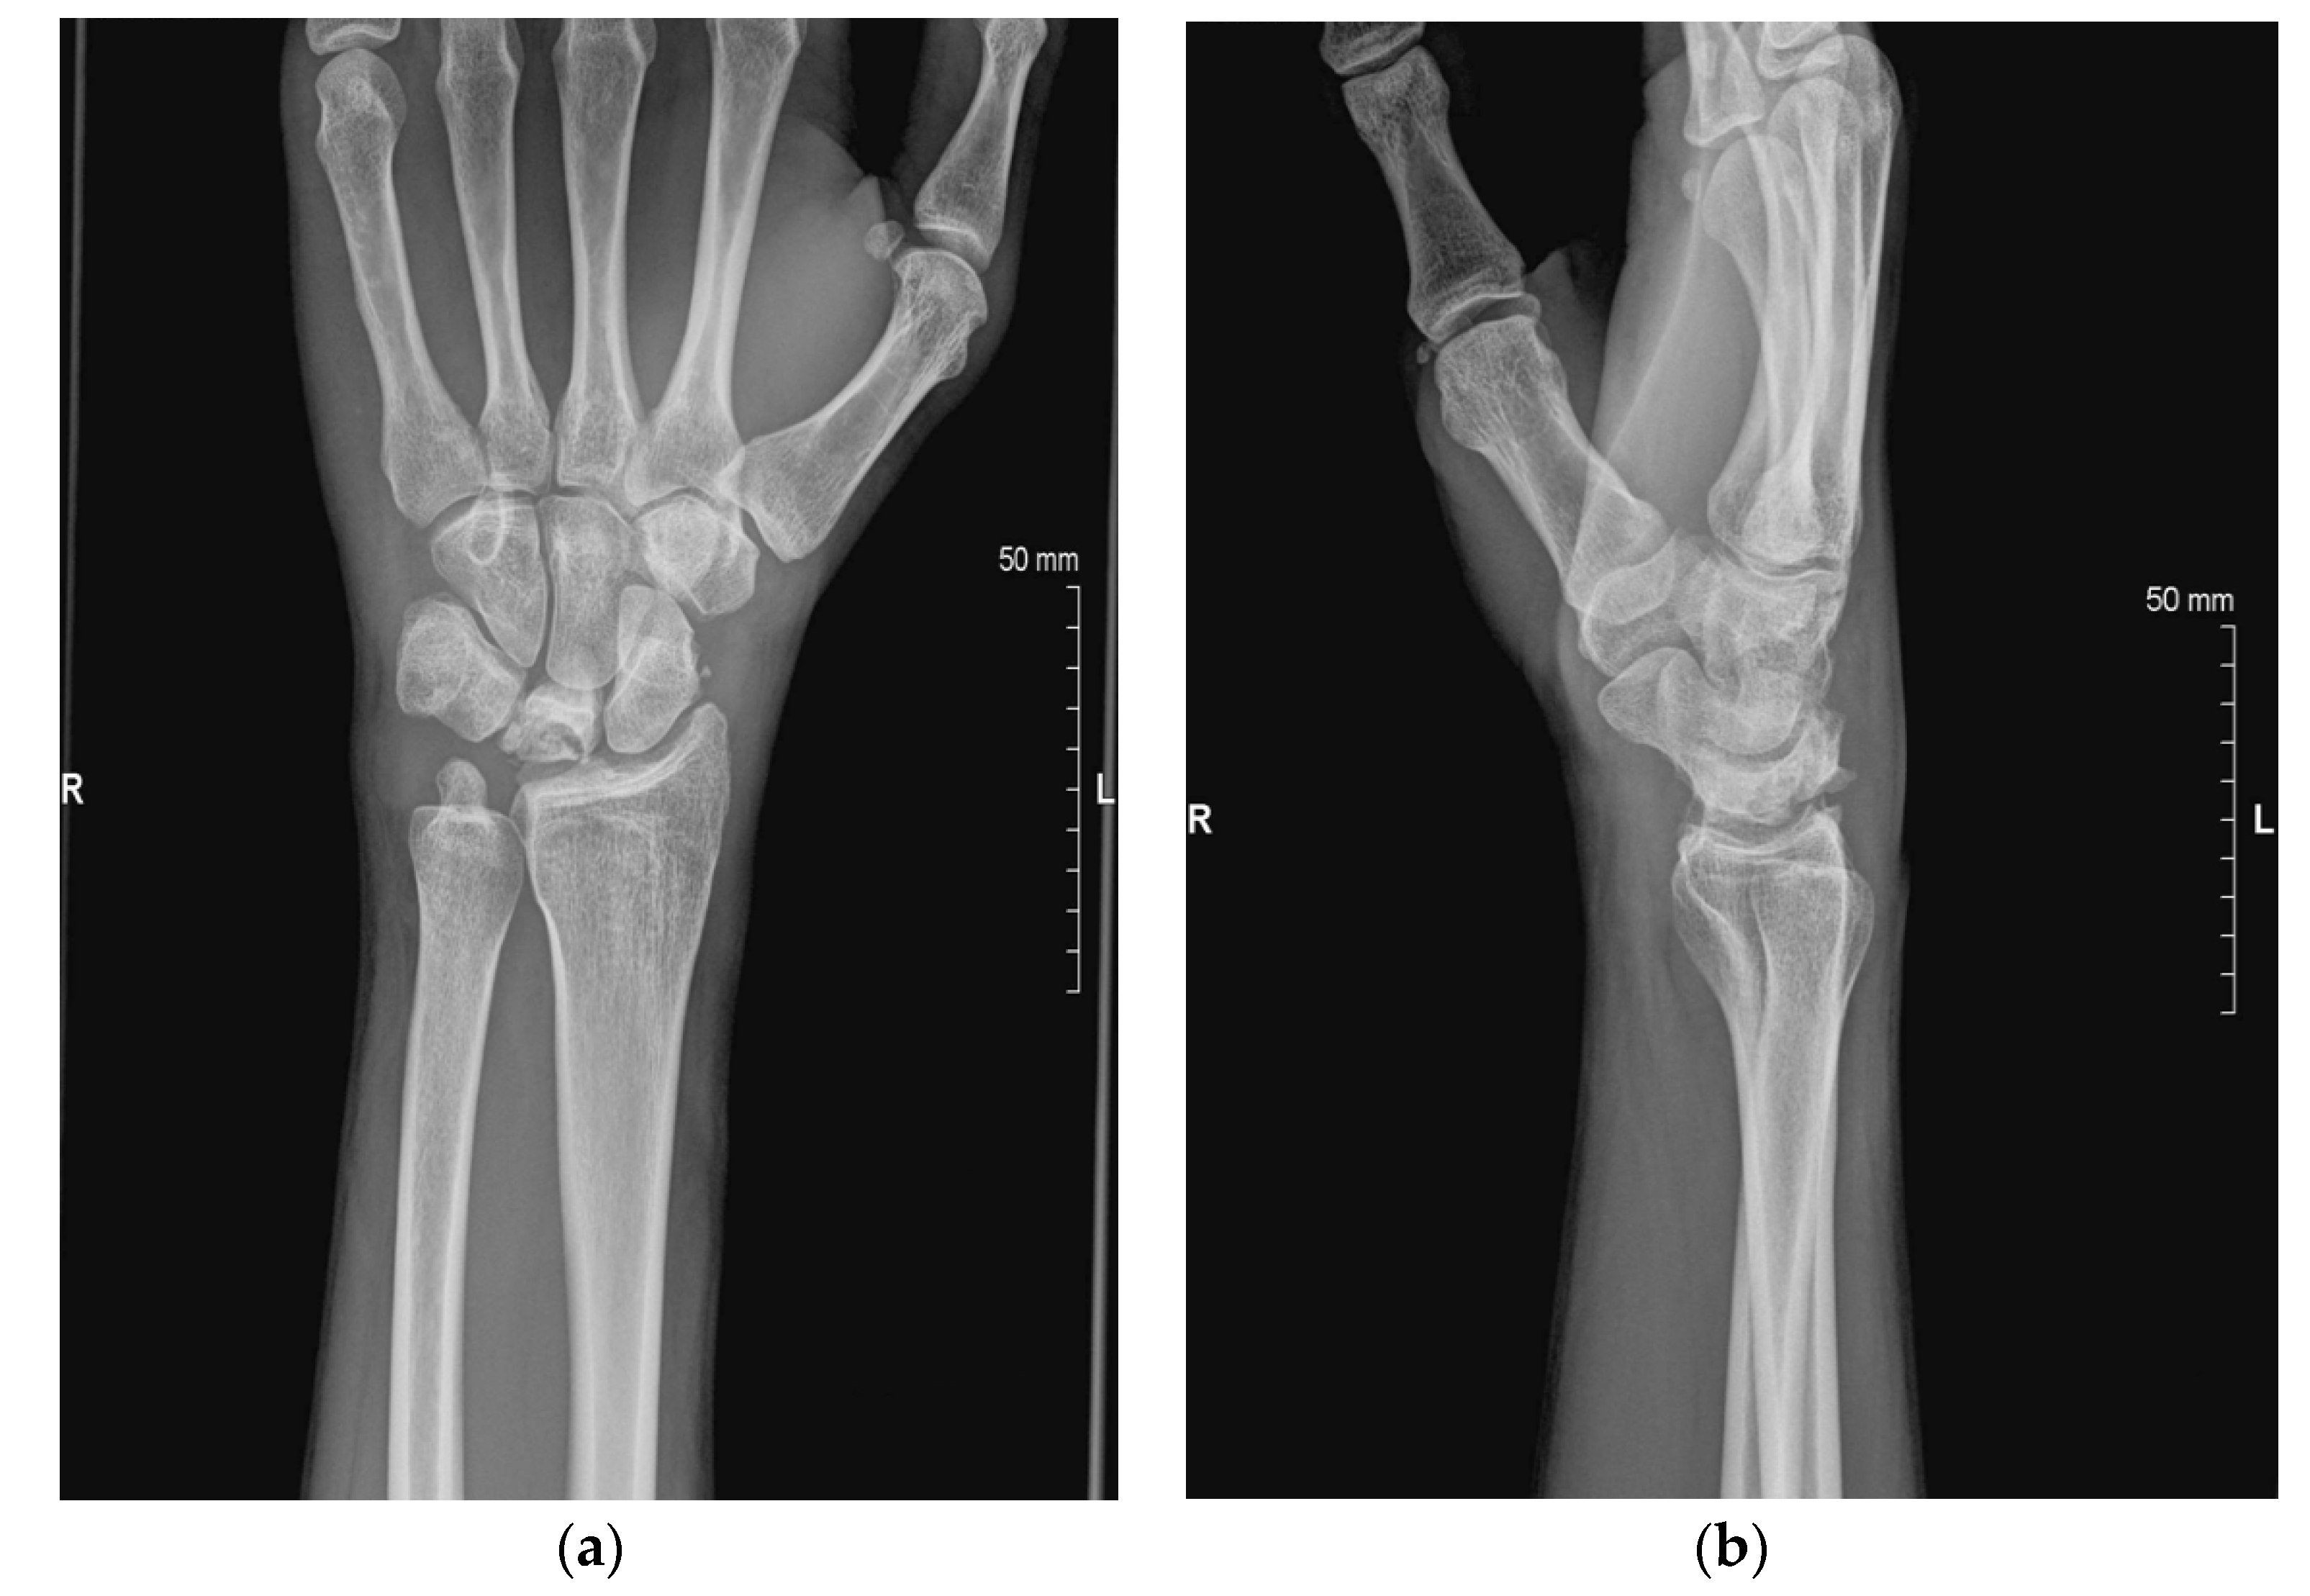

| Stage | Radiographs | MRI |

|---|---|---|

| I | Normal | ↓ T1 signal, lunate enhancement after contrast administration |

| II | Increased density without lunate collapse | ↓ T1 signal, variable T2 signal |

| IIIA | Lunate collapse, Radioscaphoid angle < 60° | ↓ T1 signal, variable T2 signal |

| IIIB | Lunate collapse with scaphoid palmar flexion (radioscaphoid angle > 60°) | ↓ T1 signal, variable T2 signal |

| IIIC | Lunate collapse with coronal lunate fracture (chronic) | ↓ T1 signal, variable T2 signal |

| IV | Lunate collapse with radiocarpal or midcarpal degenerative arthritis | ↓ T1 signal, variable T2 signal |